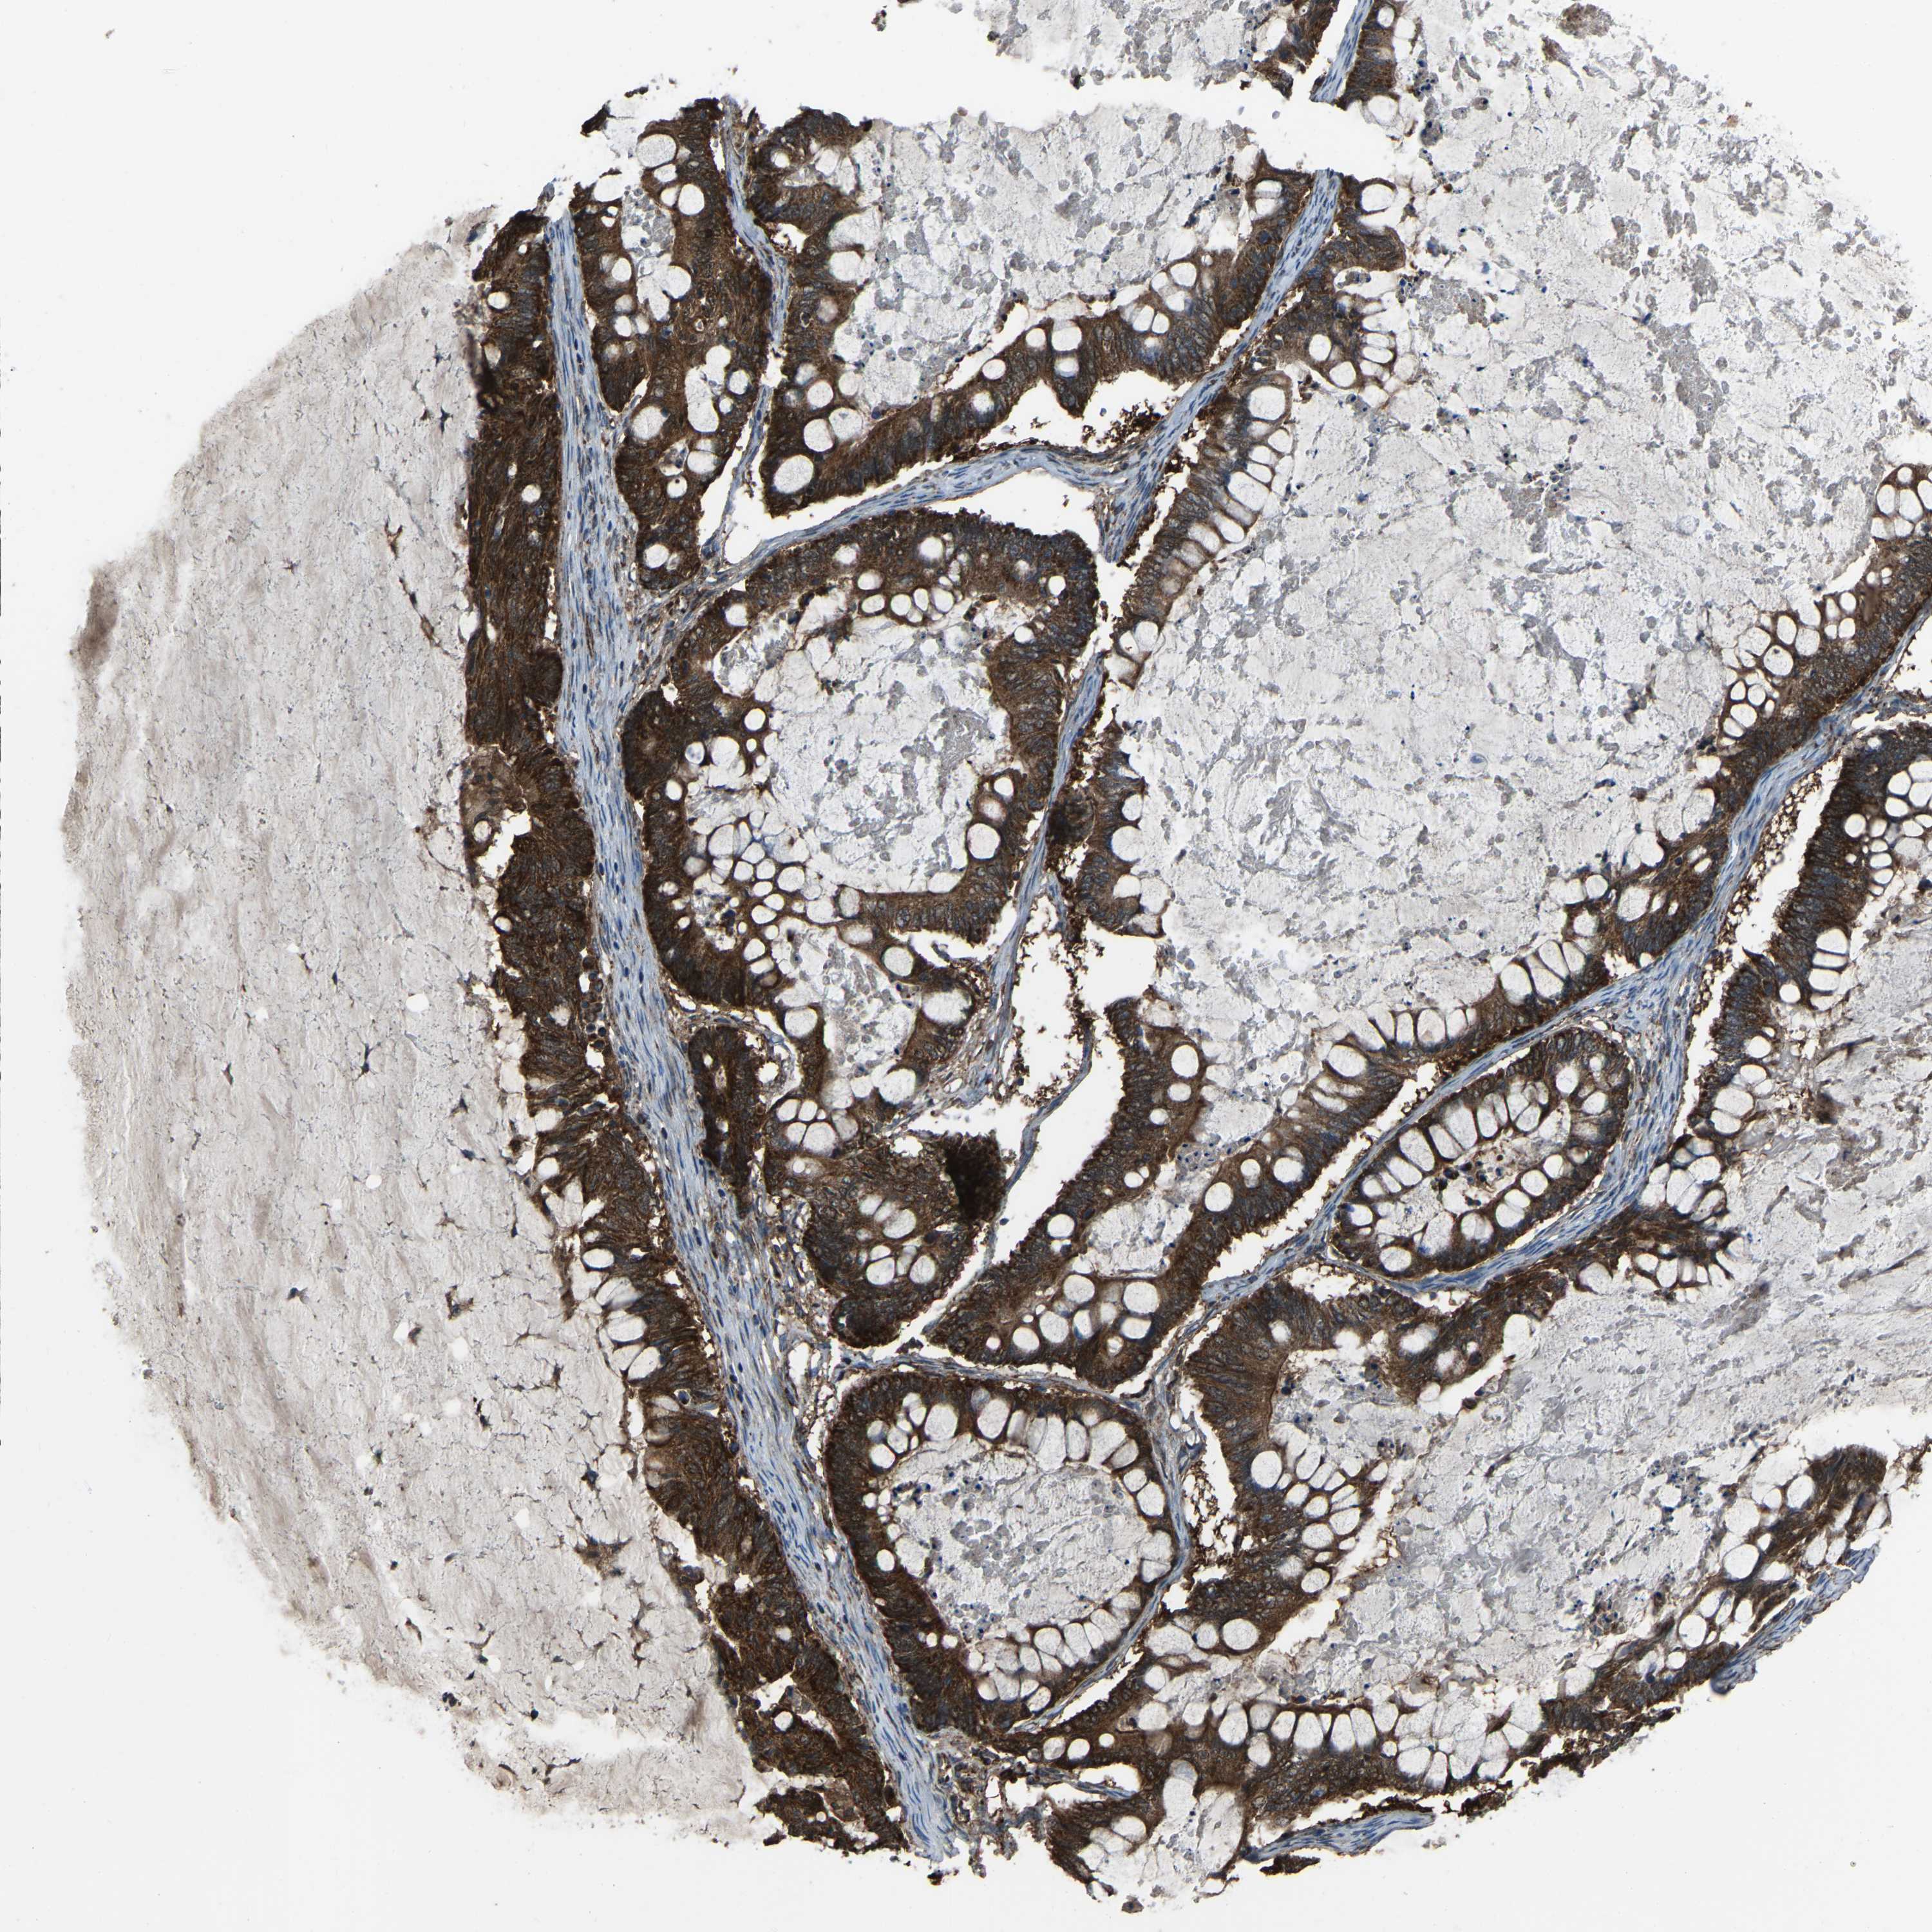

OVARIAN CANCER - Protein expressioni

A mouse-over function shows sample information and annotation data. Click on an image to view it in a full screen mode. Samples can be filtered based on level of antibody staining by selecting one or several of the following categories: high, medium, low and not detected. The assay and annotation is described here.

Note that samples used for immunohistochemistry by the Human Protein Atlas do not correspond to samples in the TCGA dataset.

Antibody stainingi

Antibody staining in the annotated cell types in the current human tissue is reported as not detected, low, medium, or high, based on conventional immunohistochemistry profiling in selected tissues. This score is based on the combination of the staining intensity and fraction of stained cells.

Each image is clickable and will lead to virtual microscopy that enables deeper exploration of all samples and also displays staining intensity scores, fraction scores and subcellular localization as well as patient and tissue information for each sample.

Antibody HPA017919

Antibody HPA019649

Antibody HPA027734

Antibody CAB006246

Cystadenocarcinoma, serous, NOS

Carcinoma, endometroid

Cystadenocarcinoma, mucinous, NOS

Carcinoma, NOS